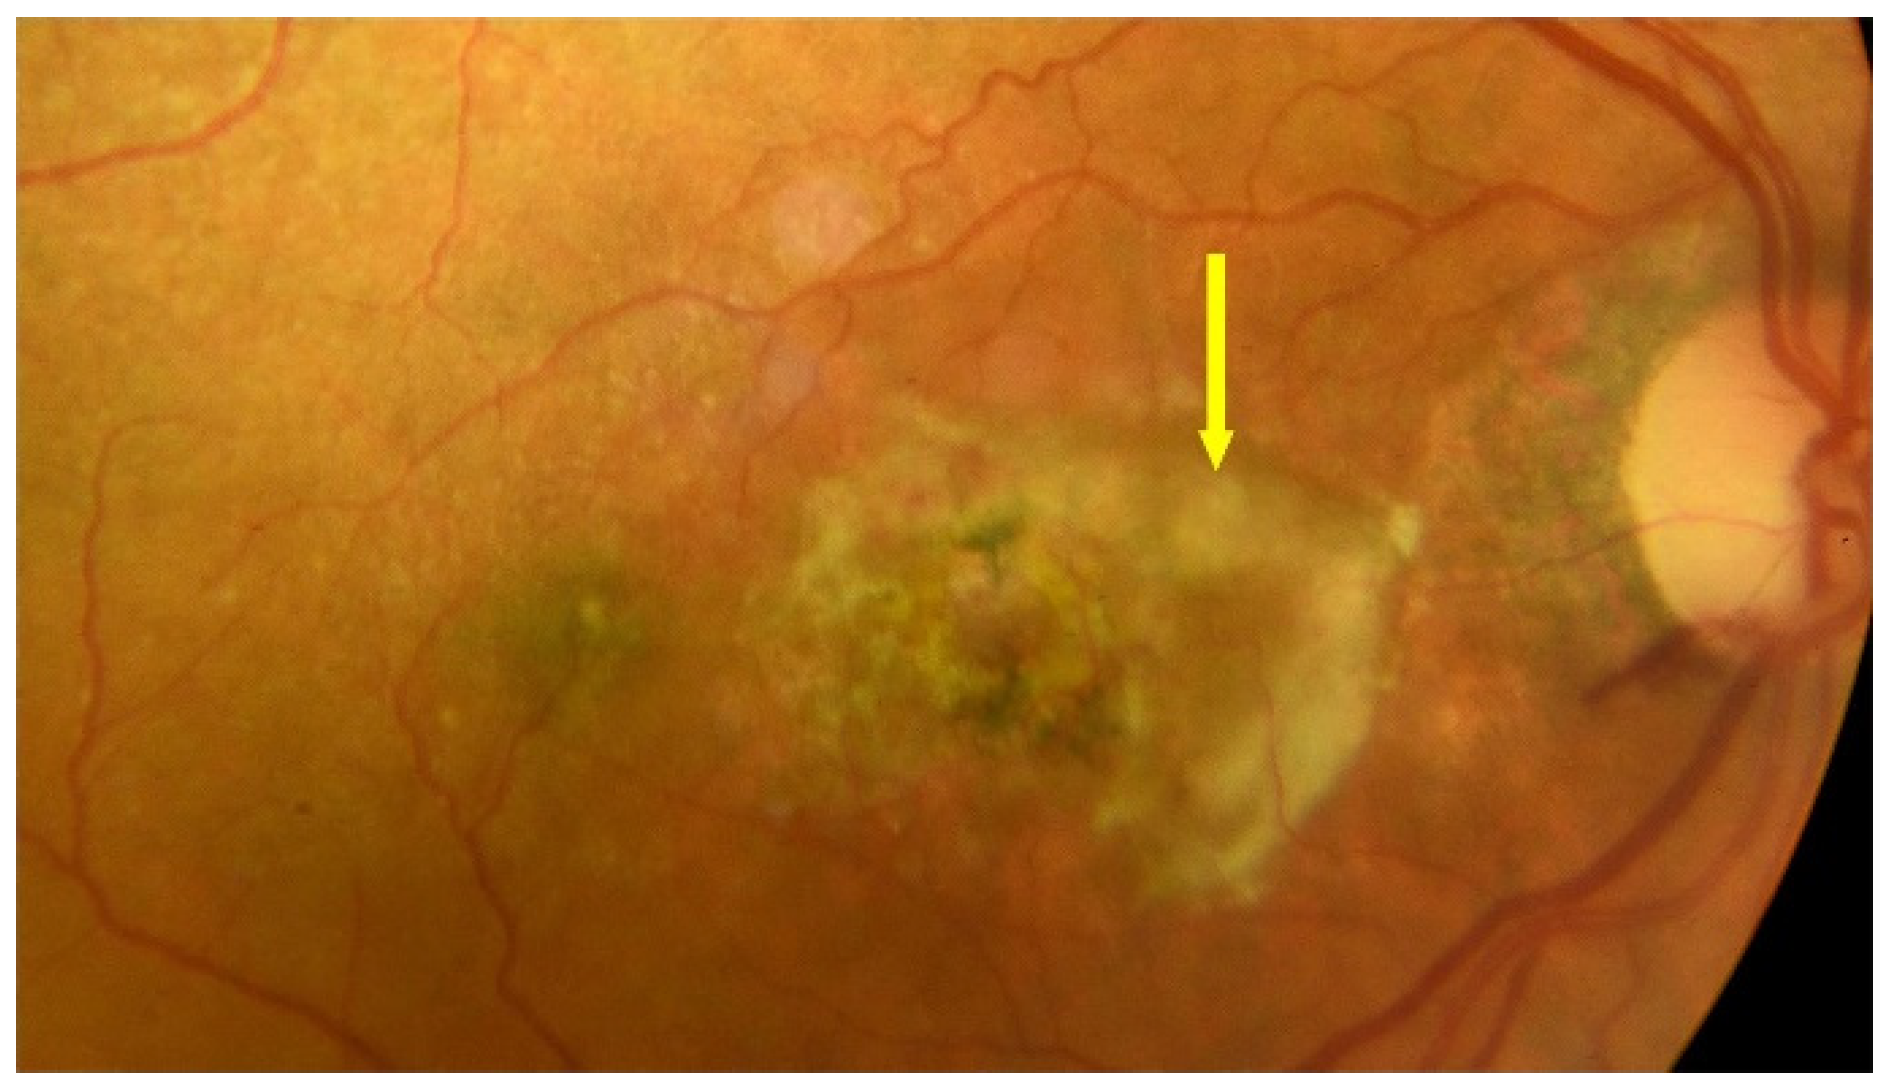

2. Treatment of Dry AMD

2.1. General Information

2.2. Drugs in Dry AMD